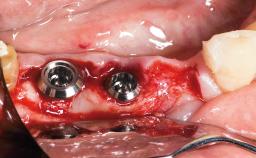

Replacement of a Maxillary Right First Molar Using an Early Loading Protocol

A 50-year-old female patient, a non-smoker, presented to the private office with a crown-restored and endodontically treated tooth, 16. Due to pain symptoms, there was a need for treatment. Another clinician had previously offered the patient a treatment option including root-canal retreatment and/or apical root resection, and she requested a second opinion. Radiographic examination revealed a less than ideal rootcanal therapy that had caused periapical osteolysis. After evaluating all the different treatment options, it was decided to extract tooth 16 and replace it with a dental implant and crown.